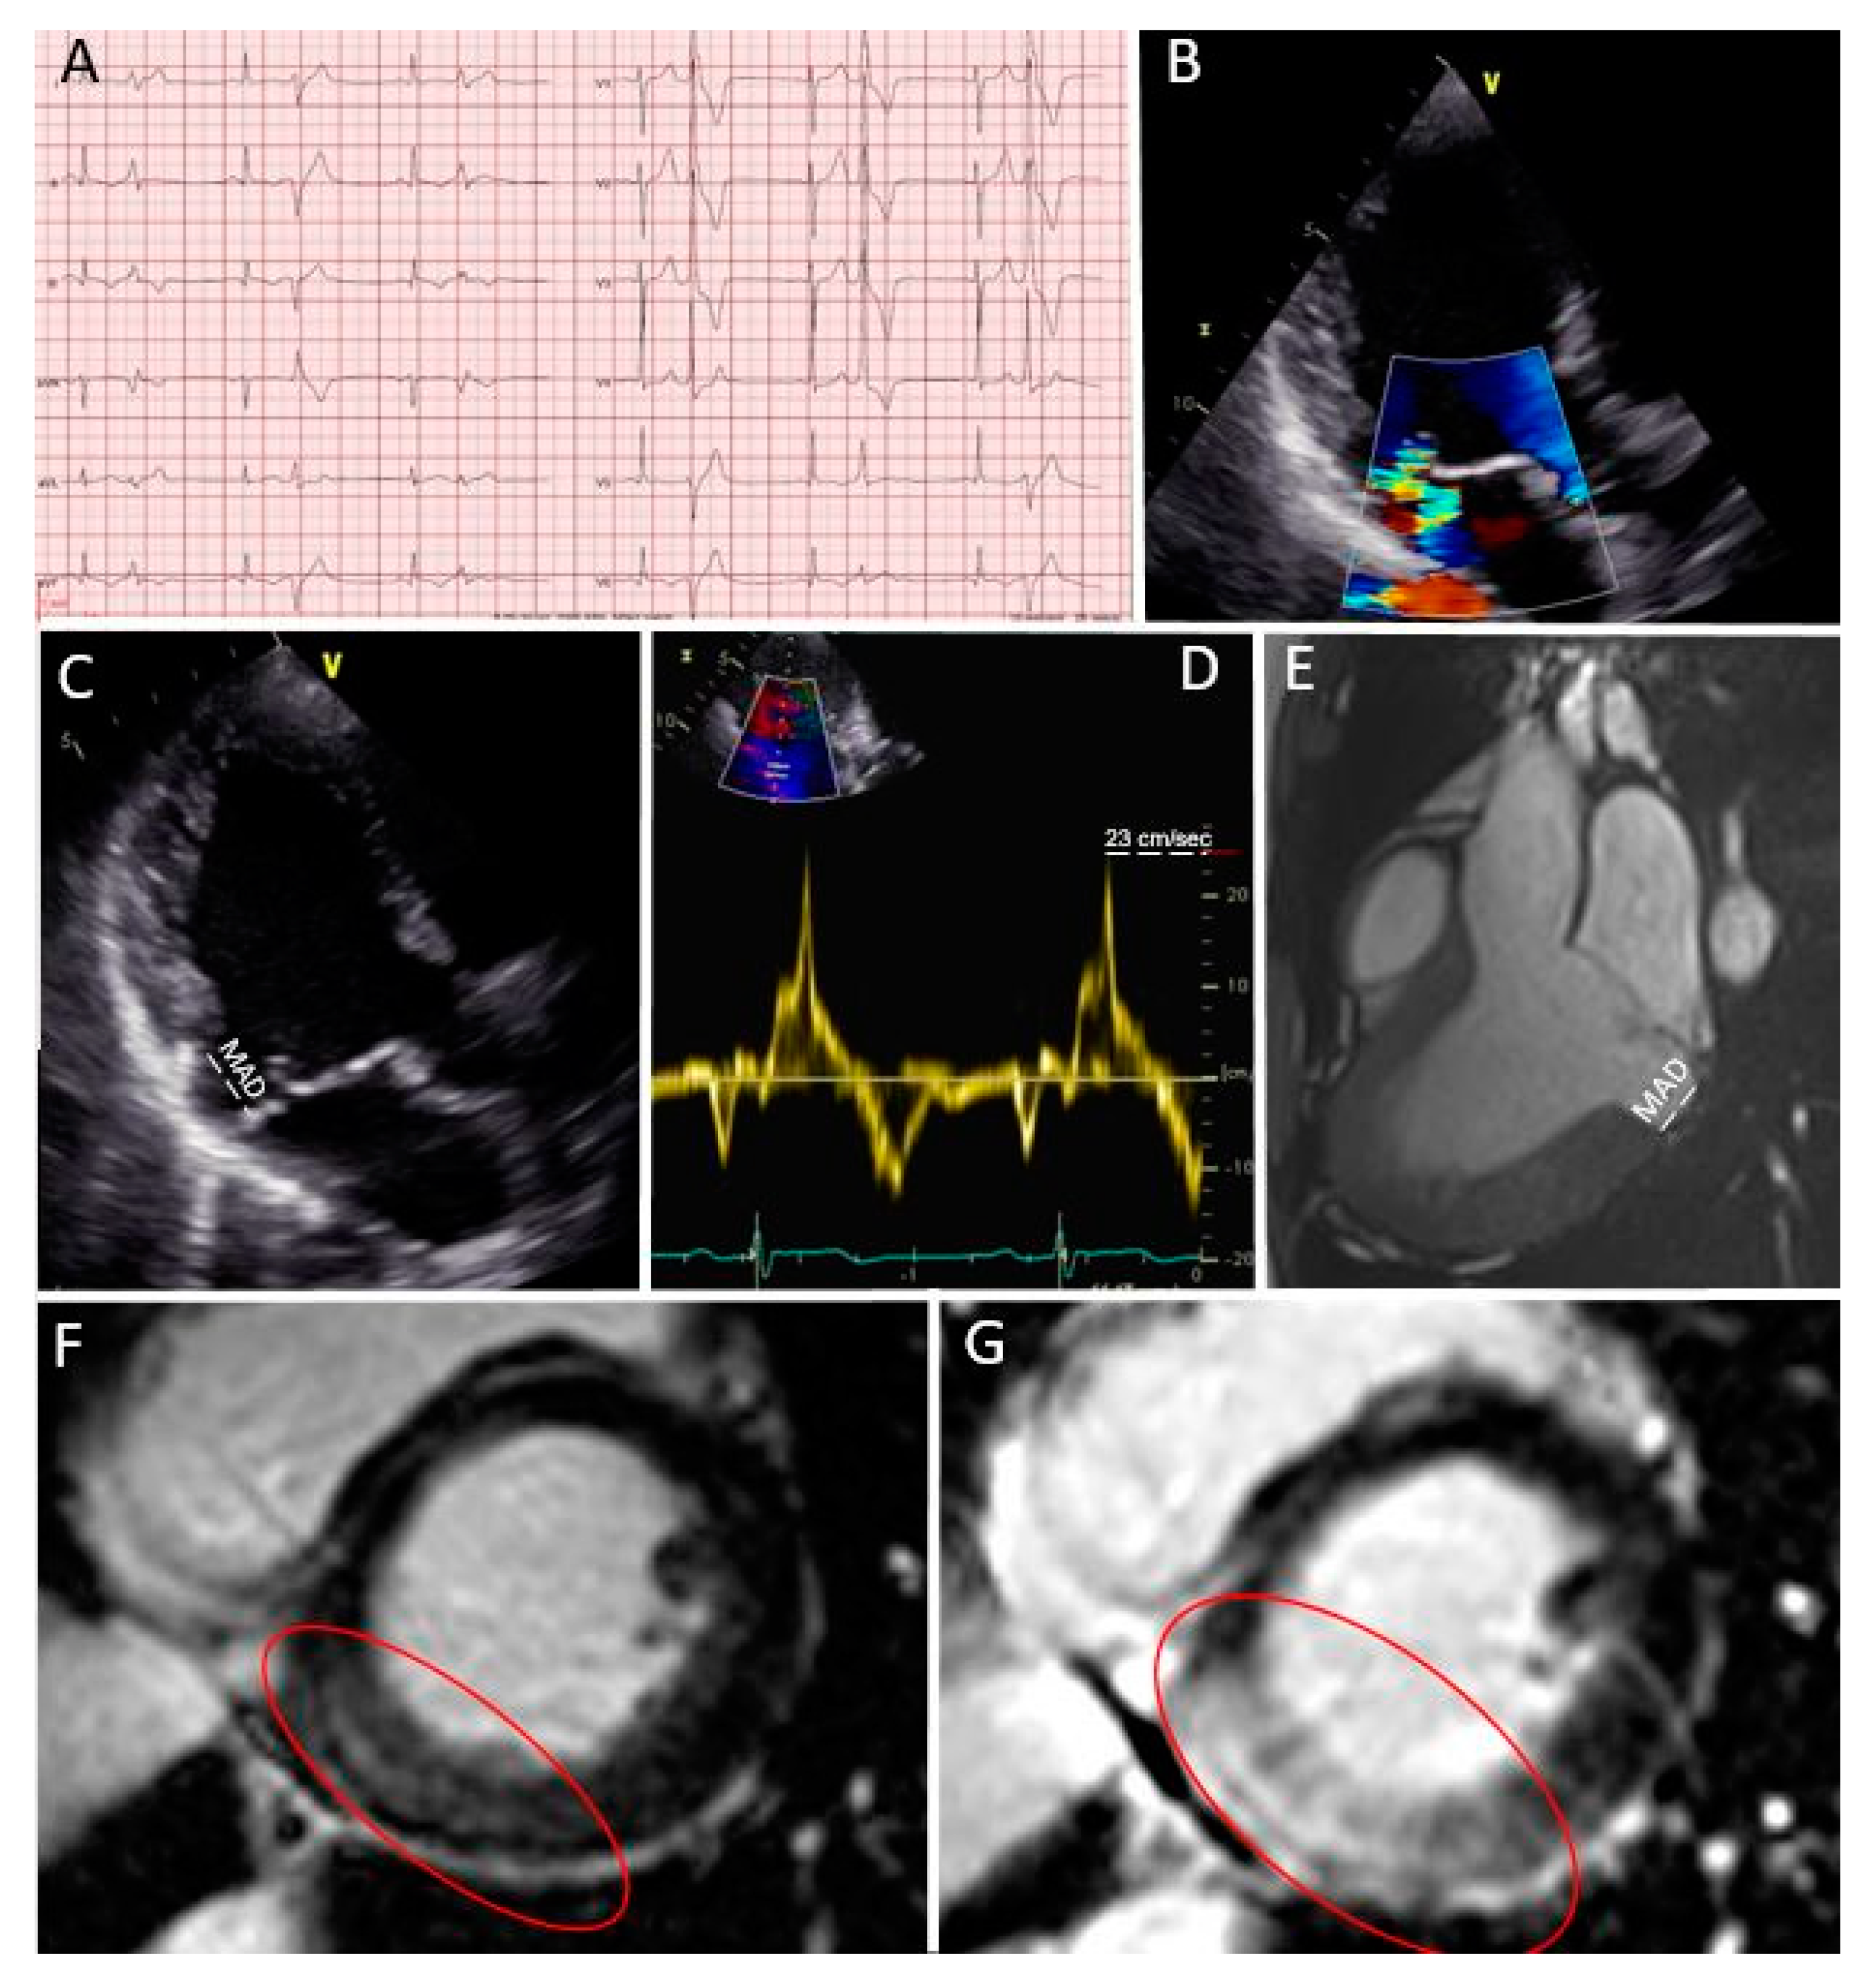

Figure 2.

Case 1: Primary prevention ICD implantation after multi-modality imaging work-up. (A) Patient’s ECG; (B) moderate mitral regurgitation during color Doppler transthoracic echocardiography; (C) bileaflet prolapse with MAD (in white); (D) “Pickelhaube sign” during transthoracic echocardiography; (E) MAD measured in a steady-state free precession three-chamber view during CMR; (F,G) a large zone of fibrosis in the basal inferior wall in LGE sequences (red circle).

A 22 year-old female patient was known for mitral valve prolapse since infancy. Her baseline ECG showed negative T waves in the infero-lateral leads (Figure 2A) and mitral regurgitation during echocardiography was moderate (Figure 2B). She was symptomatic for mild palpitations. However, several “red flags” were present (female sex and baseline ECG), as well as a bileaflet prolapse with MAD (Figure 2C) and a Pickelhaube sign (Figure 2D) during transthoracic echocardiography. Considering the patient’s symptoms and the presence of “red flags” in the baseline assessment, she underwent a 24 ECG Holter examination, which showed the presence of several ventricular extrasystoles (>20,000), and the CMR study confirmed the presence of MAD (Figure 2E). In addition, a large zone of fibrosis in the basal inferior wall was visible (Figure 2F,G red circle). The extracellular volume was high in all basal left ventricular segments. In this case, with several “red flags,” an invasive electrophysiology study (EPS) study was undertaken to more precisely stratify the arrhythmic risk. The EPS showed the induction of ventricular tachycardia and even ventricular fibrillation. For this reason, a subcutaneous implantable cardioverter defibrillator (ICD) for primary prevention was finally implanted. The patient was also treated with 2.5 mg of bisoprolol, and a reduction in ventricular arrhythmias was documented at follow-up.